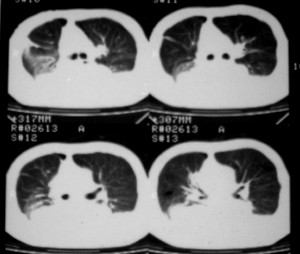

m ,60岁,右上肺ca术后一月。

纵隔淋巴结增大,双侧胸水。考虑术后残留,而非复发。

肝及右肾转移瘤,双侧胸水

肺癌术后 。双侧胸水 纵隔 胸膜 肝脏转移